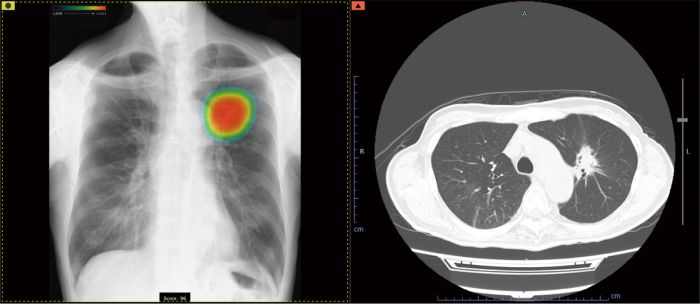

CXR-AID

AI技術を活用し、健診・診療時の

胸部単純X線画像診断を支援

撮影した胸部単純X線画像を自動解析。

対象の10所見が疑われる領域を検出しマーキング。

その領域を医師が再確認することで、見落とし防止を支援します。